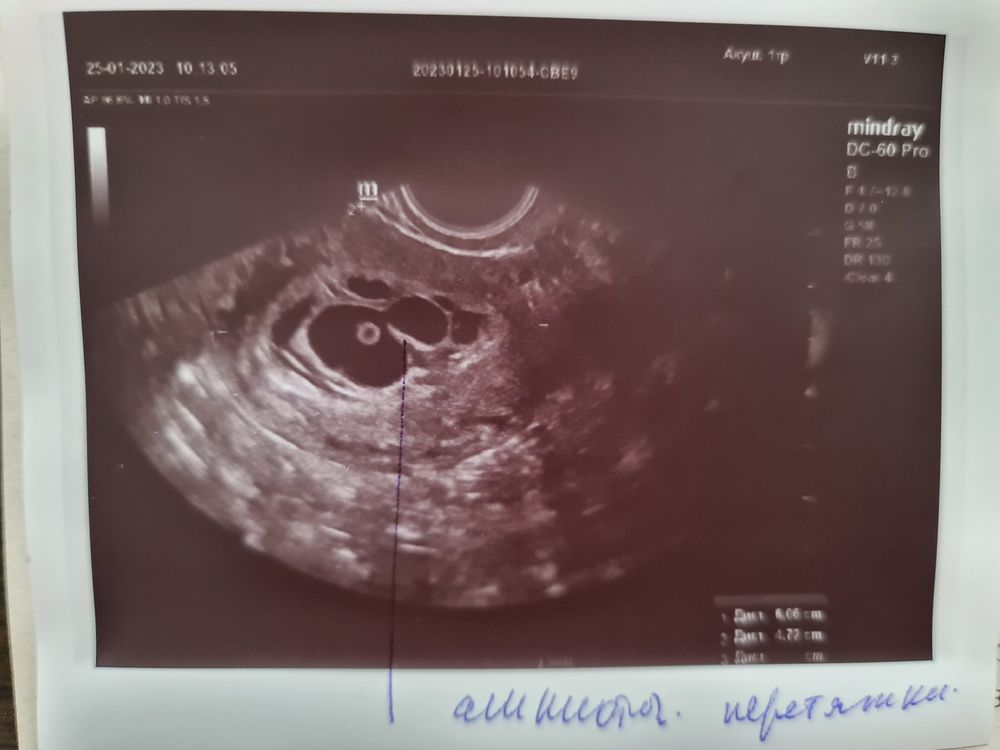

Амниотическая перетяжка

Девочки , всем привет , может кто нибудь сталкивался с подобным, поделитесь, пожалуйста, своим опытом . Сходила я на УЗИ ,срок 6 недель 5 дней и узистка долго молча смотрела ,искала ,я уж напугалась ,думала что внематочная , но потом она успокоила , ПЯ в матке, эмбрион соответствует сроку, есть сердцебиение, но плодное яйцо деформировано и есть амниотическая перетяжка. Отправила меня в медико - генетический центр. Ох не спокойно мне теперь (((